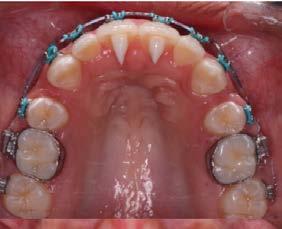

Objetivo: presentar un caso clínico de paciente con mordida abierta anterior, clase II y deglución atípica tratada con aparatología fija ortodóntica.

Caso clínico: paciente femenino de 19 años, patrón dolicofacial, perfil convexo, clase II esqueletal debido a una retrusión mandibular, mordida abierta anterior esqueletal, clase II molar, clase canina no establecida por mordida abierta, apiñamiento severo superior e inferior y deglución atípica.

Resultados: obtención de una clase canina I y clase molar II funcional, se corrigieron las sobremordidas horizontal y vertical, y se logró la coincidencia de líneas medias facial y dental. El manejo de la mordida abierta anterior se llevó a cabo por medio de la corrección del hábito de deglución atípica con la ayuda de spikes de resina, elásticos intermaxilares y arcos utility, y se obtuvieron buenos resultados estéticos, dentales y funcionales.

Al examen intraoral se observa arcada dental incompleta; con ausencia de órganos dentales 16 y 27 (Figura 1).